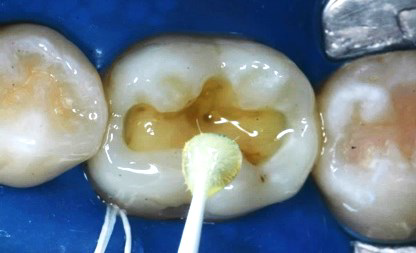

A Figura abaixo mostra a aplicação de uma das etapas do sistema adesivo convencional de 2 passos. Tendo em vista esta ser uma etapa bastante crítica para o sucesso clínico da restauração de resina composta, muitos cuidados são necessários na aplicação do sistema adesivo.

Com relação aos cuidados clínicos e a aplicação do sistema adesivo convencional de 2 passos assinale a alternativa correta.